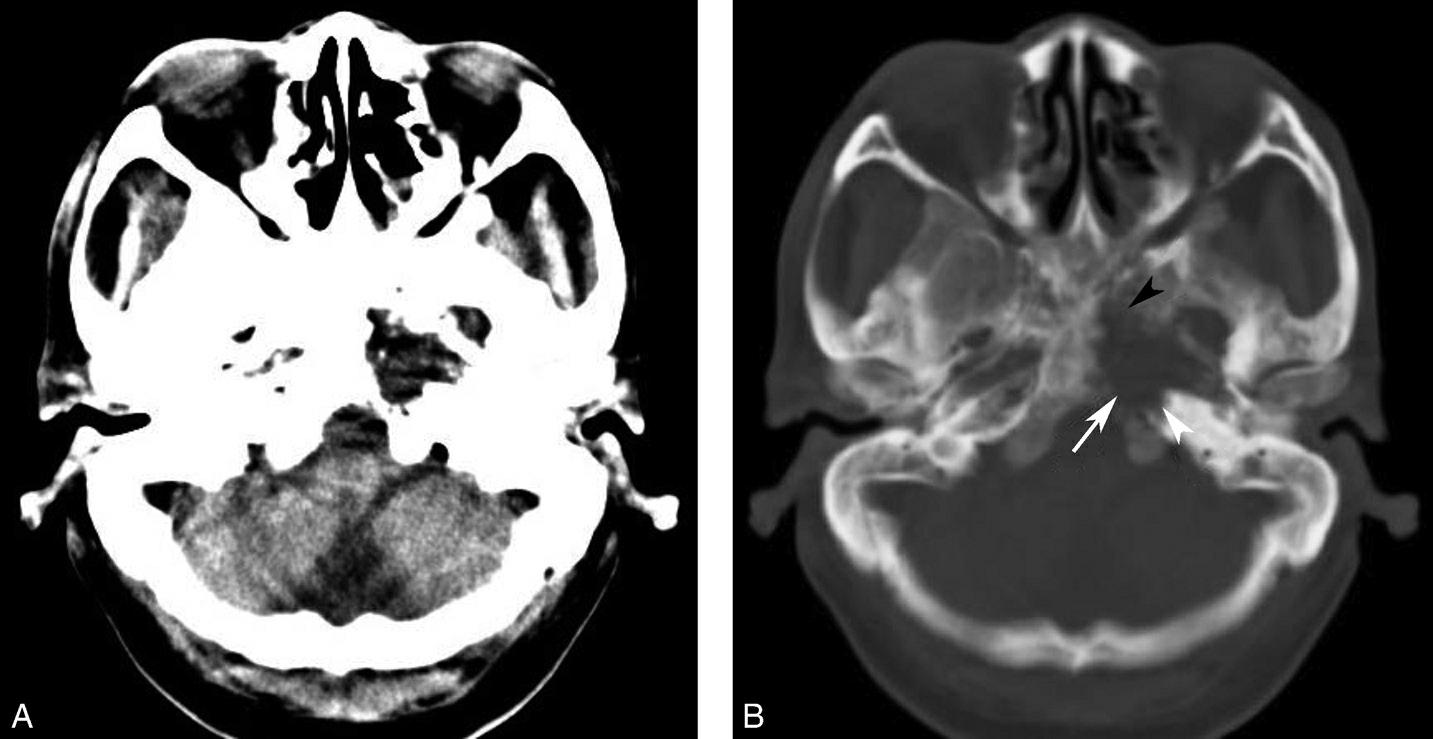

破裂孔、卵圆孔、棘孔及斜坡等均为重要的解剖结构,临床常见疾病如鼻咽癌常侵犯上述结构(图1-2-3)。颈静脉孔区较常见的肿瘤为颈静脉球瘤,常伴有颈静脉孔及其邻近骨质的破坏(图1-2-4)。

图1-2-3 鼻咽癌颅底骨质破坏

A.横断面;B.横断面(骨窗)

骨窗示左侧岩尖、斜坡、左侧蝶骨大翼骨质破坏、受侵(白箭),肿瘤经破裂孔侵入颅内(黑箭头)

图1-2-4 右侧颈静脉球瘤

A.横断面(骨窗);B.横断面

右侧颈静脉孔区不规则骨质破坏(箭),局部见软组织肿块(☆)